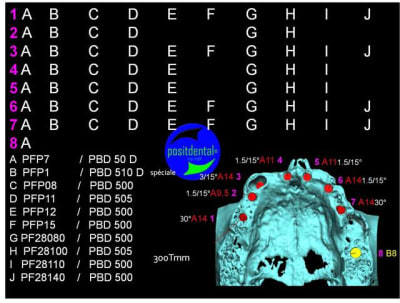

en attendant la pano voici les coupes de la S.I.A.O.

Image33_nwzawb.jpg

Image34_ixvkww.jpg

Image35_orinjf.jpg

Image39_nacsid.jpg

Image40_hkzycw.jpg

Image41_egzryy.jpg

Image42_p57obk.jpg

Image43_jgylho.jpg

Image44_ysqyf8.jpg

Image45_d112br.jpg

Image46_u9eg6l.jpg

Image47_yffnwq.jpg

Image48_ptc9lw.jpg

Image30_exkkml.jpg

Image31_p13zyn.jpg

Image32_ffzd3q.jpg

Image36_jfzwrz.jpg

Image37_inavxh.jpg

Image38_jfa54w.jpg

bien...mais dans certaines zones,surtout postérieures, j'aurais mis plus gros...surtout qu'il y a la place...